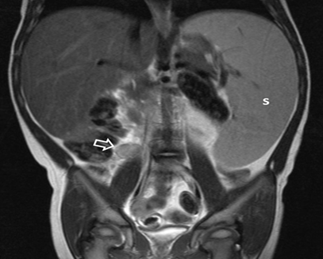

abdominal MRI confirmed isolated excessive splenomegaly without significant

intra-abdominal lymphadenopathy (Figure

Figure 2: Abdominal MRI scan, Tw-w sequence, coronal plane. The

spleen (S) is excessively large, extending to the left lower abdomen. There is

also isolated mild lymphadenopathy (arrow) at the upper limits of normal for

this location (1 cm short axis).